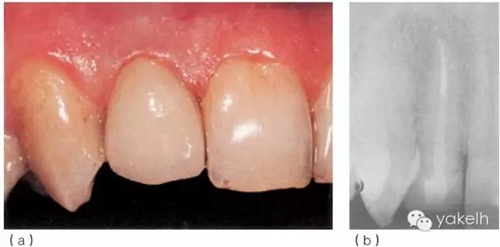

¤¤首先,使用超聲器械清理根管,確保樁道內(nèi)的根管壁上沒有牙膠及根管封閉劑殘留;通過試戴,選擇合適的纖維樁(圖6.3.5a);酒精擦拭樁道后,進行酸蝕、沖洗、干燥;使用復合樹脂粘結(jié)劑粘樁(圖6.3.5b),光固化(圖6.3.5c);在樁及剩余牙體表面涂布牙本質(zhì)粘結(jié)劑,逐層堆塑樹脂核;樹脂核完成后,即刻行冠部預備(圖6.3.5d);制取印模,使用術(shù)前模型制作丙烯酸臨時冠;拍攝術(shù)后X線片(圖6.3.5e);2周后復診,粘固永久性全冠(圖6.3.6a);1年后復查,患者無不適,根尖X線片顯示患牙根尖周組織正常(圖6.3.6b)。

圖6.3.6(a)粘固永久性全冠。(b)12術(shù)后1年復查X線片。